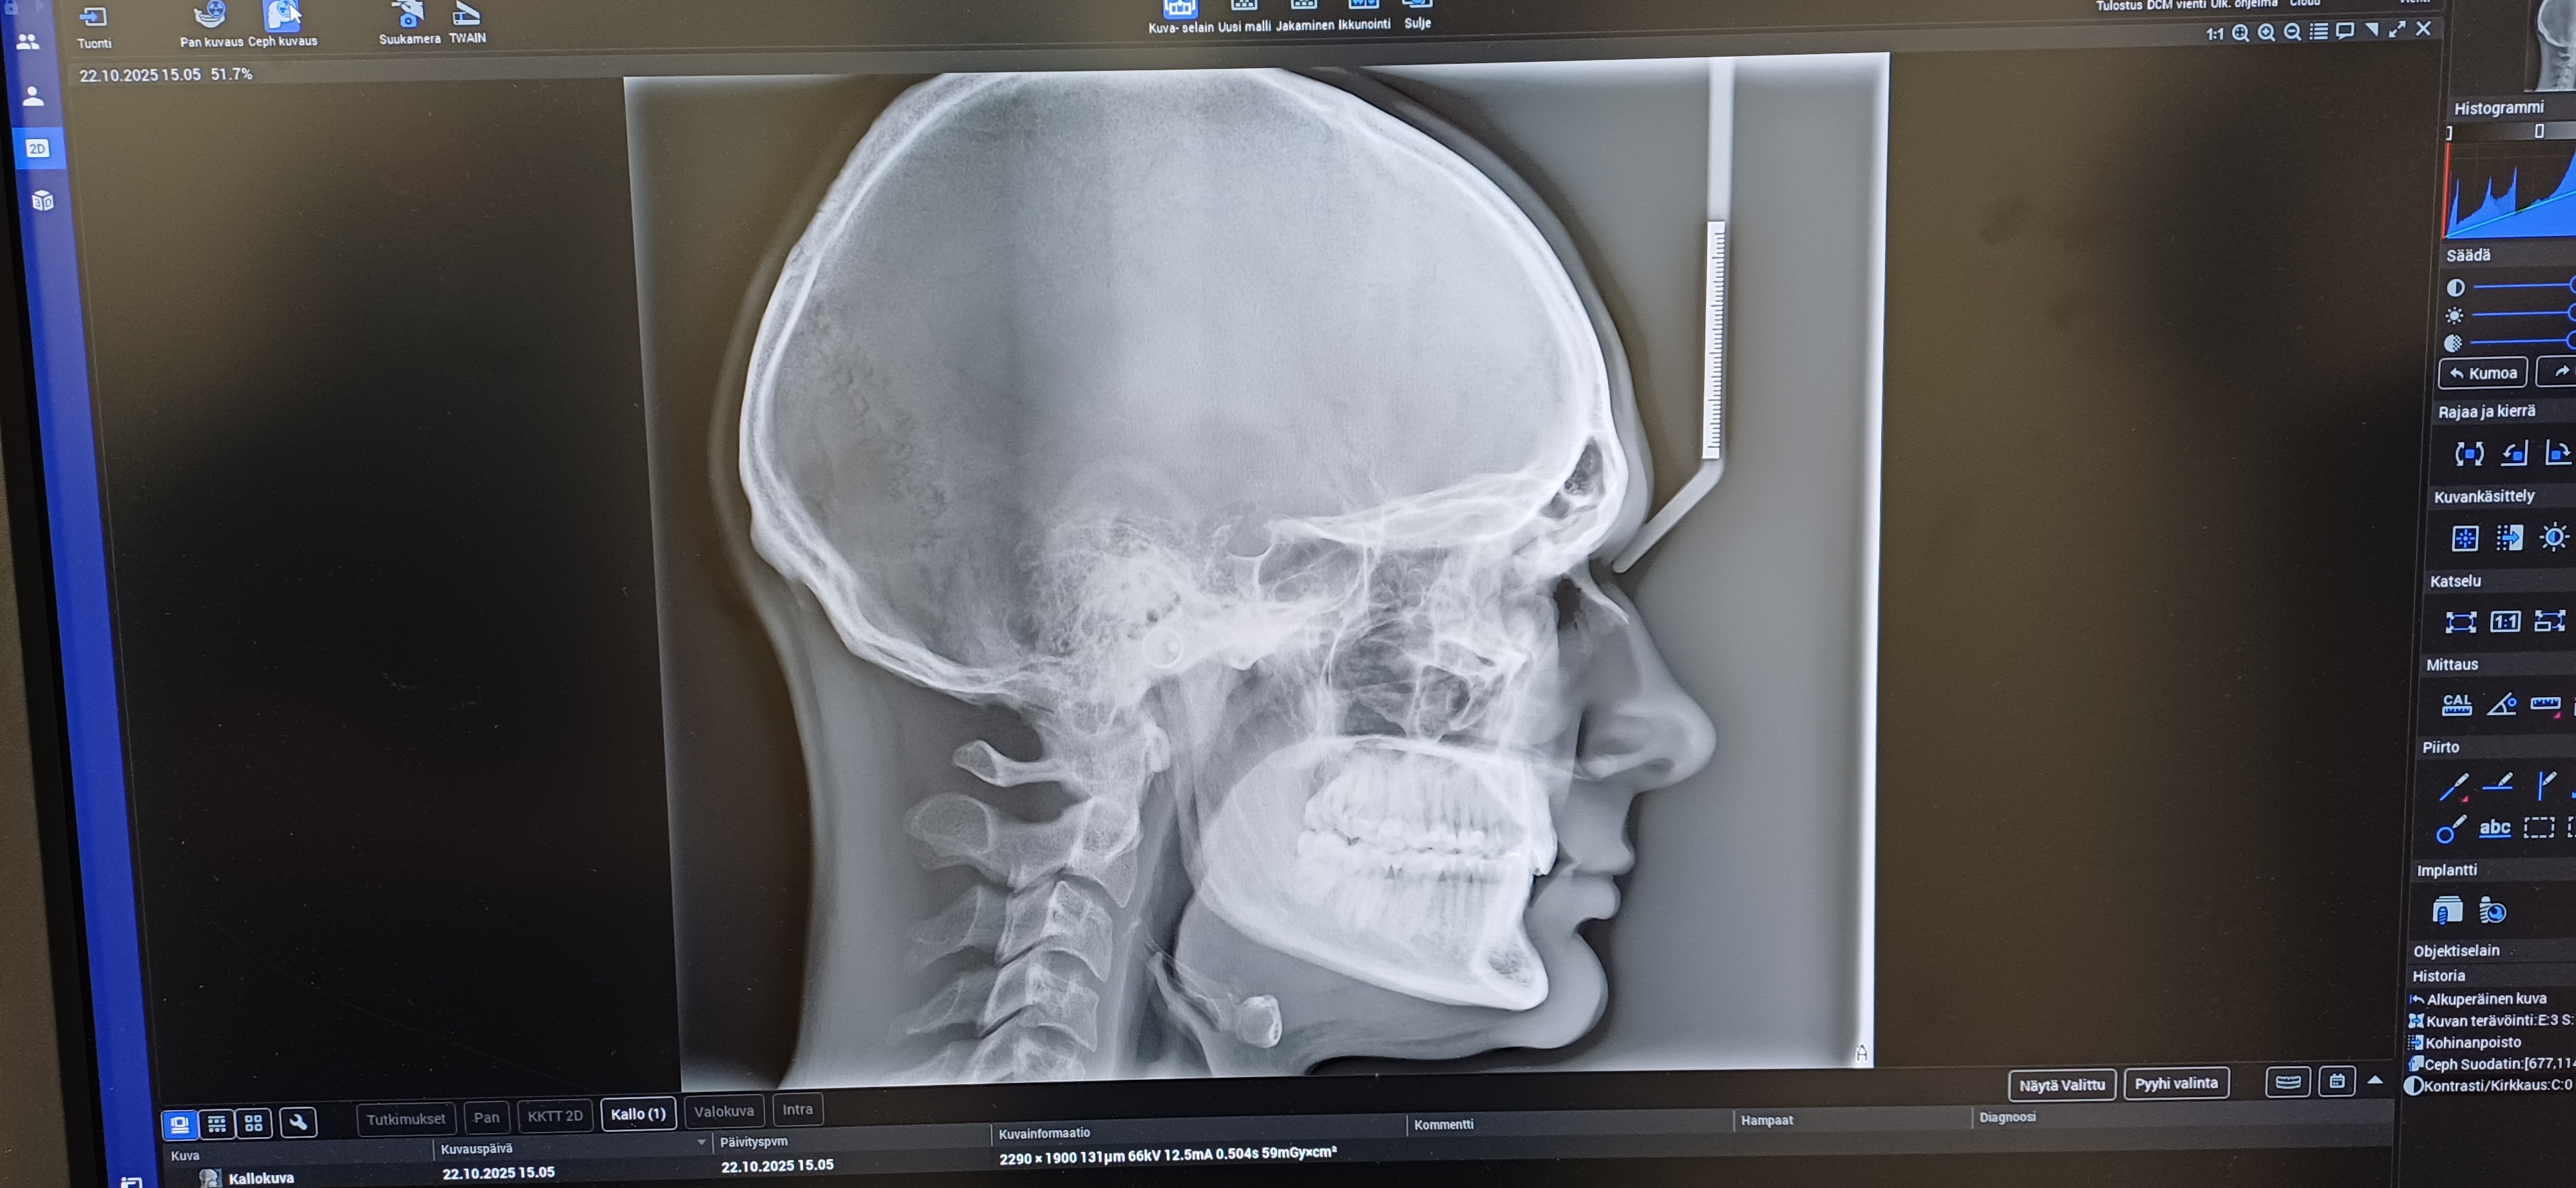

About to go into orthodontics to fix my overbite, but if the problem is skeletal to also fix my jaw/jaws through surgery. What do you guys think? Am i recessed?

About to go into orthodontics to fix my overbite, but if the problem is skeletal to also fix my jaw/jaws through surgery. What do you guys think? Am i recessed?